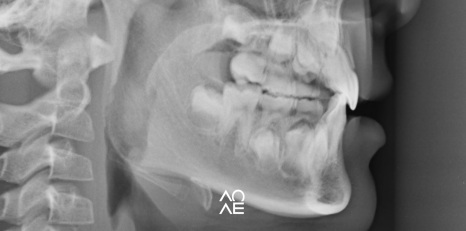

특히나, 성장기 어린이에게는

페이스 마스크 (Face Mask) 라는

장치를 사용하기도 하는데요

보기에는 Face Mask 가 조금은

부담스러워 보일 수 있는데요

하악 성장 방향을 전방에서 뒤 그리고

아래 방향으로 최전 시키고, 상악 성장을

전방으로 유도해내는 견인 장치로

구강 내 장착하는 것과

안면부에 장착하는 장치로

구성이 되어 있는데요

사람마다 골의 성장 속도도 다르고

사용을 위한 환경도 달라서요

어느 나이때가 가장 좋다.

이렇게 말씀드리기는 어렵고요

하지만, 다양한 연구 결과를 보면

만 8~9세 이전에 사용하는게 좋다고는

알려져 있지만, 주치의 선생님과의

정확한 검사를 통해서 장치 유무를

결정하시는 것이 좋을 것 같습니다